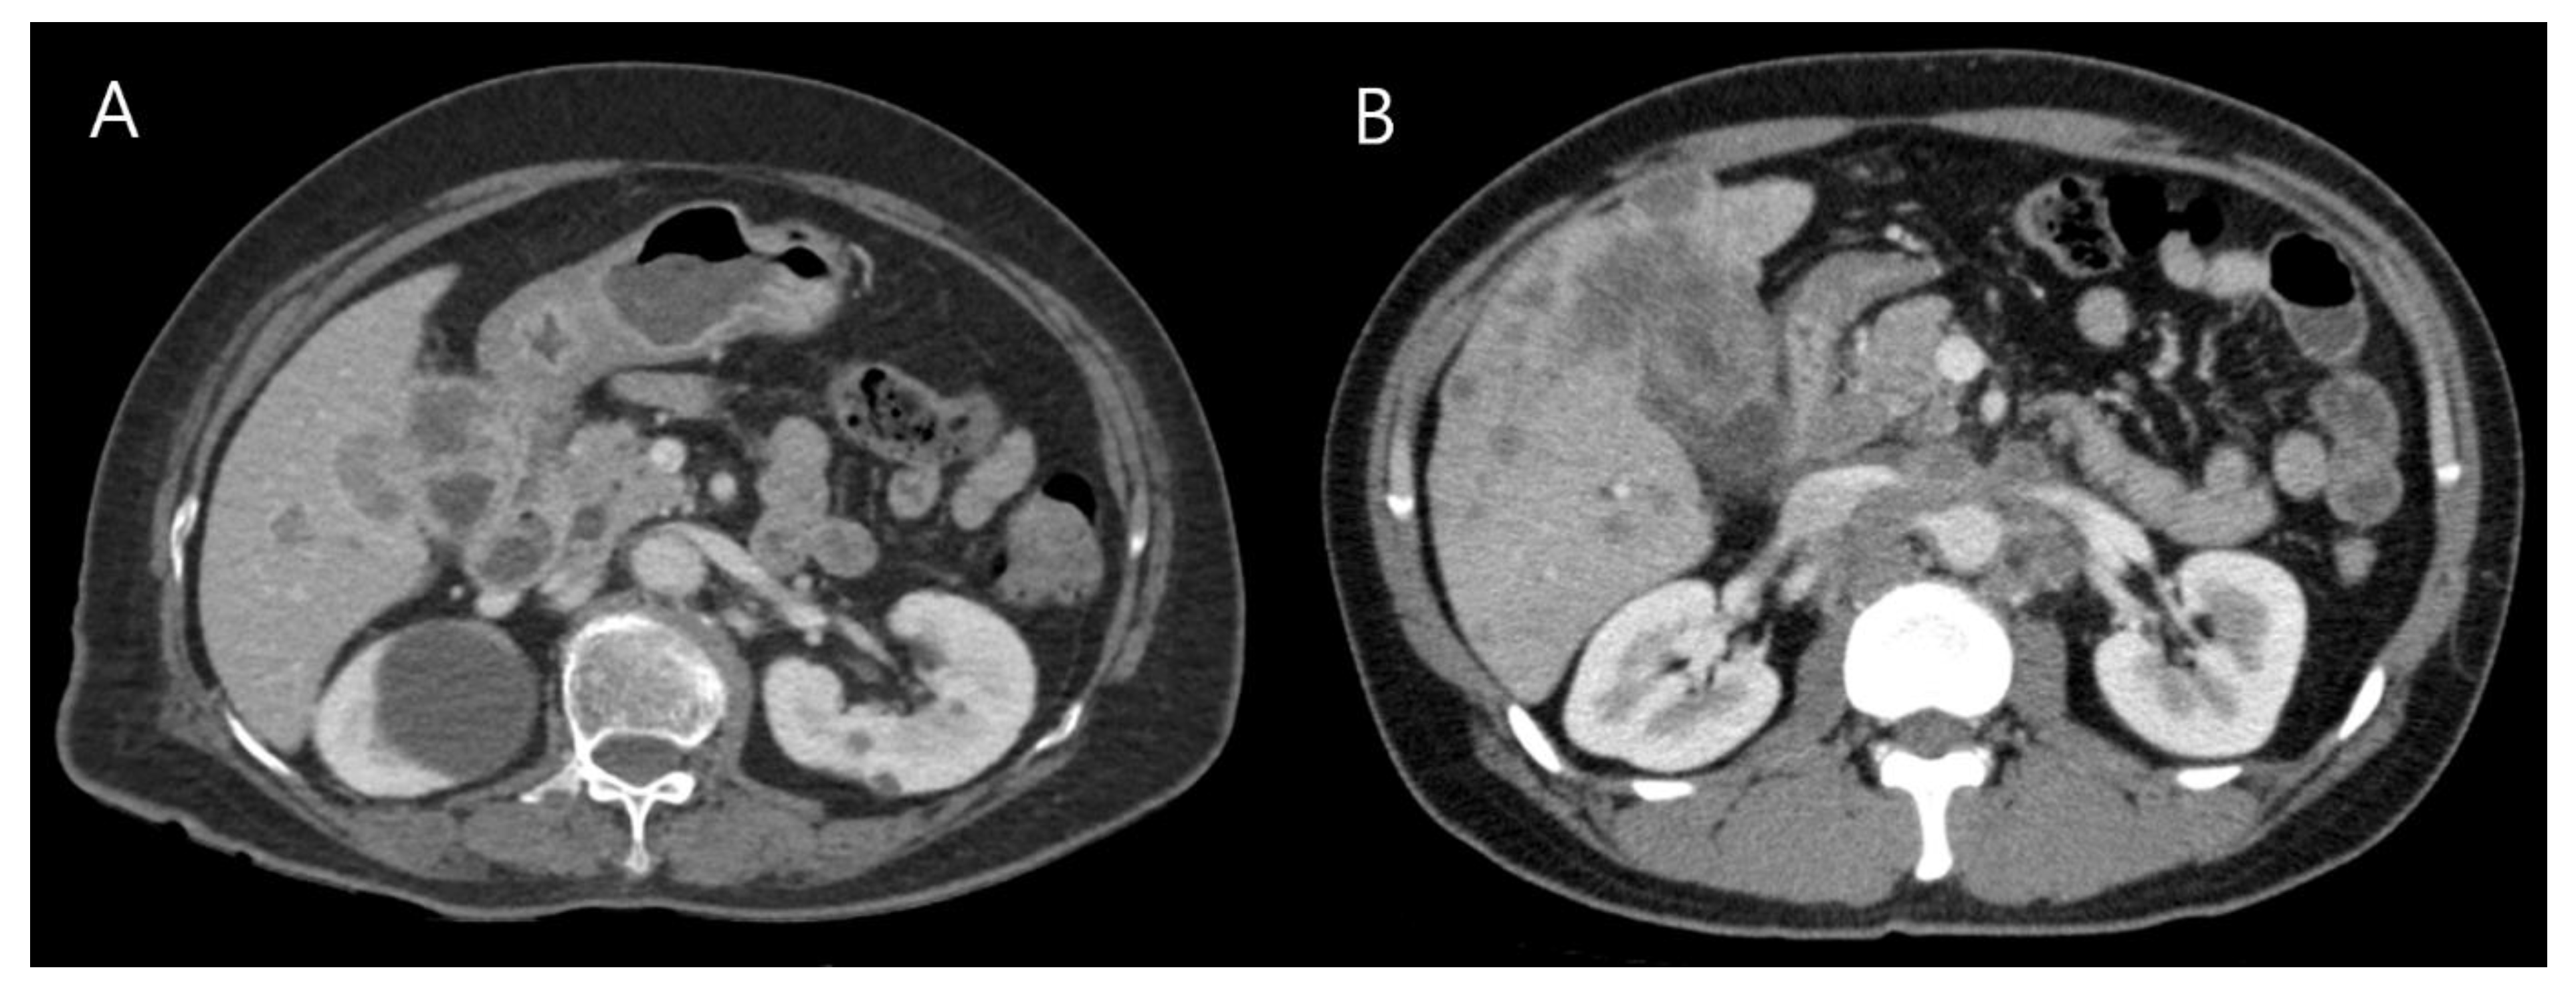

- Kim, T.-H.; Kim, S.H.; Lee, K.B.; Han, J.K. Outcome and CT differentiation of gallbladder neuroendocrine tumours from adenocarcinomas. Eur. Radiol. 2017, 27, 507–517. [Google Scholar] [CrossRef]